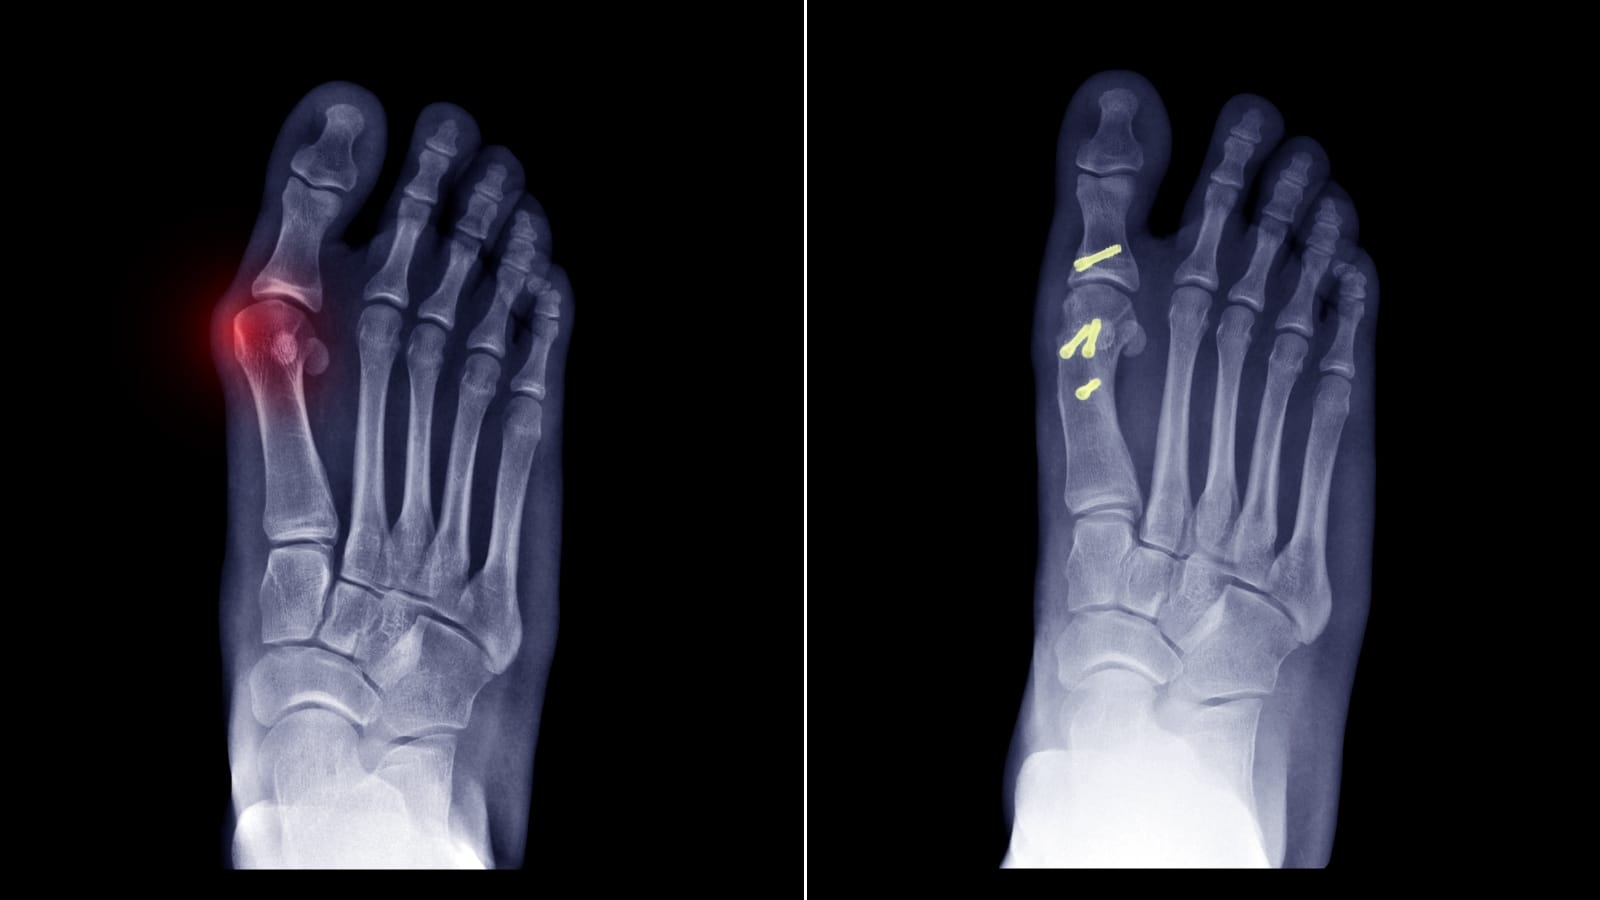

Hastada röntgen cihazı ve scopi cihazı kontrolünde hastanın birinci tarak kemiğin üzerinde belli bölgeleri işaretleyerek küçük açılımlar yapılmaktadır. Buradan kabaca 1 cm’lik iki tane açılım yaparak, tarak kemiğin içindeki açık ameliyatta gerçekleştirdiğimiz o kesilerin özel aletler yardımıyla kapalı yöntemle yapılır. Bu 1 santimetrelik açtığımız alanlarda işaretlemelerimizi yapıyor, röntgen cihazı üstünden kemiğin nereden keseceğimizi tespit ediyoruz tespitini yapıyoruz. Tespit yaptıktan sonra kesilerimizi kapalı yöntemle yapmış oluyoruz. Yine aynı şekilde açık ameliyatta kullandığımız gibi vidalarla tespit etmemiz gerekmektedir. Bu tespitleri yaparken de yine özel cihazlar vasıtasıyla bu vidaları kapalı olarak göndermekteyiz. Hep “özel cihazlar” kelimesini kullanılmasının nedeni; minimal invaziv cerrahi yapılırken en önemli şey buna uygun bir setin varlığının olmasıdır. Bu set olmadan minimal invaziv cerrahinin gerçekleştirilmesi mümkün değildir. Setin ve teknik aksamın varlığında ancak gerçekleştirilebilen bir cerrahi yöntemdir. O yüzden minimal invaziv cerrahi yaparken setin olması bizim için çok çok önemli ve kıymetli bir nokta.